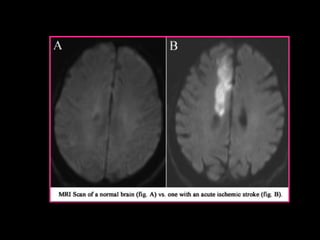

Brain cells usually die within an hour of the onset of a stoke but may survive for several hours, especially when the blood supply to the brain has not been stopped completely. Sometimes the interruption resolves itself quickly and, if this occurs within about an hour, it is known as a mini- stroke or a transient ischaemic attack (TIA). A mini stroke is an early warning sign of a more serious stroke where 30% of stroke patients will have a small warning episode of a TIA and sufferers will experience similar symptoms to a normal stroke such as the sudden loss of function of a particular part of the body. The difference between a TIA and a stroke is that in a TIA the symptoms disappear completely within 24 hours. In 75% of cases the symptoms clear within one hour, often within only a few minutes, because the blockage in the artery clears itself very quickly before the affected brain tissue has died.  30% of people have damage evident on sensitive brain imaging techniques such as MRI after the mini- stroke.

Brain cells usuallydie within an hour of the onset of a stoke but may survive for several hours, especially when the blood supply to the brain has not been stopped completely. Sometimes the interruption resolves itself quickly and, if this occurs within about an hour, it is known as a mini- stroke or a transient ischaemic attack (TIA). A mini stroke is an early warning sign of a more serious stroke where 30% of stroke patients will have a small warning episode of a TIA and sufferers will experience similar symptoms to a normal stroke such as the sudden loss of function of a particular part of the body. The difference between a TIA and a stroke is that in a TIA the symptoms disappear completely within 24 hours. In 75% of cases the symptoms clear within one hour, often within only a few minutes, because the blockage in the artery clears itself very quickly before the affected brain tissue has died.  30% of people have damage evident on sensitive brain imaging techniques such as MRI after the mini- stroke.